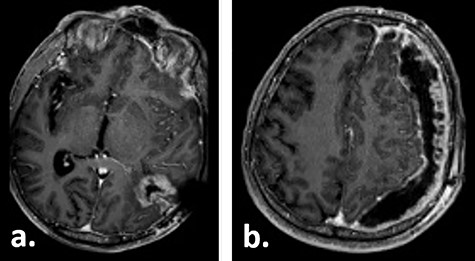

Ten weeks postoperatively, the patient complained of vertigo and a self-limiting episode of right-sided visual field restriction and neglect. Subsequently, oral cortisone therapy was started again, which lead to the relief of these symptoms. The MRI showed a new contrast enhancement around the resection cavity, possibly treatment-related after radiochemotherapy, as well as a 14-mm-thick, left-sided subdural fluid collection causing a midline shift of 6 mm, which was interpreted as a subdural hygroma or hematoma (Fig. 2). The latter was slightly progressive on a CT scan 1 week later, and surgical evacuation through a burr hole was indicated. Intraoperatively, it presented as a slightly xanthochrome, slightly pressurized subdural hygroma. No pathological alterations of the dura were revealed during this procedure. Postoperatively, the subdural hygroma was incompletely regressive and began to grow again as was seen on the CT images 3 weeks after the surgery. This finding was considered to be related to post-radiation changes. The patient stayed asymptomatic and received two cycles of adjuvant chemotherapy with temozolomide 150 mg/m2 body surface area and 200 mg/m2 body surface, respectively.

Gadolinium-enhanced T1-weighted axial MRI of the patient 10 weeks after tumour resection demonstrating the resection cavity (a) and new subdural fluid collection (b).

Fifteen weeks after tumour resection and 4 weeks after hygroma evacuation, the patient presented again with concentration loss, fatigue and a moderate right-sided hemiparesis. A new CT scan revealed a strongly progressive subdural hygroma with a 3-mm-thick subdural membrane. The hygroma was evacuated through the same burr hole; however, due to an unsatisfying hygroma regression, a subduro–peritoneal shunt for permanent hygroma drainage was implanted subsequently. During these both procedures, a thick greyish subdural membrane was noticed, but no tissue samples were taken. Despite the volume reduction of the hygroma, its membrane still caused a considerable mass effect. Few days after the last surgical procedure, a cerebral MRI was performed following the tumour follow-up protocol. On this imaging, the subdural membrane over the left hemisphere presented as an inhomogeneous contrast-enhancing lesion with irregular contours (Fig. 3).

Gadolinium-enhanced T1-weighted axial MRI of the patient 16 weeks after tumour resection demonstrating the resection cavity (a) and progressive subdural fluid collection with the newly occurred contrast-enhancing membrane (b).